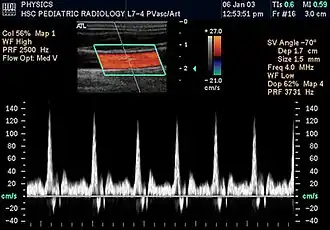

Duplex ultrasonography sometimes refers to Doppler ultrasonography or spectral Doppler ultrasonography.[3] Doppler ultrasonography consists of two components: brightness mode (B-mode) showing anatomy of the organs, and Doppler mode (showing blood flow) superimposed on the B-mode. Meanwhile, spectral Doppler ultrasonography consists of three components: B-mode, Doppler mode, and spectral waveform displayed at the lower half of the image. Therefore, "duplex ultrasonography" is a misnomer for spectral Doppler ultrasonography, and more exact name should be "triplex ultrasonography".[3]

Colour Doppler shows the direction of the blood flow in red or blue (either towards or away from the transducer). Meanwhile, spectral Doppler not only shows the direction of blood flow, it also shows the phases (pulsatility) and acceleration of the blood flow. Any sudden changes in direction of blood flow produces audible sounds on the ultrasound machine.[3]

In spectral Doppler, the y-axis shows the direction and velocity of the flow. Meanwhile, the x-axis (as known as "baseline") shows the flow over time. The gradient at any point on the waveform would therefore shows the acceleration of the flow. In "antegrade" flow, the blood flows according to the normal flow within the circulatory system (e.g. veins flow towards the heart while arteries flows away from the heart). In "retrograde" flow, the flow would reverse (e.g. veins flow away from heart or arteries flow towards the heart). However, "retrograde" flow can be both abnormal or normal. For example, in portal hypertension, there is an abnormal portal venous flow where it flows away from the liver (hepatofugal flow) instead of the normal flow towards liver (hepatopetal flow). In jugular venous pressure waveform of the internal jugular vein, the retrograde "a" waveform is a normal flow due to right atrium contraction. Both antegrade or retrograde flow can be either towards or away from the probe transducer, depending on the position of the probe relative to the blood flow. Blood flow toward the transducer would appear above the baseline while blood flows away from the transducer will appear below the baseline. Waveform of the flow can be classified as: pulsatile (as in arteries), phasic (as in veins), non-phasic (as in diseased veins), and aphasic (no flow). Spectral broadening (thickness of the waveform) increases from large vessels (plug flow) to medium vessels (laminar flow) to small/stenotic/diseased vessels (turbulent flow) due to a larger variety of blood with different ranges of velocities in those with turbulent flow.[3]

Doppler ultrasonography is widely used in renal ultrasonography. Renal vessels are easily depicted by the color Doppler technique in order to evaluate perfusion. Applying spectral Doppler to the renal artery and selected interlobular arteries, peak systolic velocities, resistive index, and acceleration curves can be estimated (Figure 4) (e.g., peak systolic velocity of the renal artery above 180 cm/s is a predictor of renal artery stenosis of more than 60%, and a resistive index, which is a calculated from peak systolic and end systolic velocity, above 0.70 is indicative of abnormal renovascular resistance).[12]